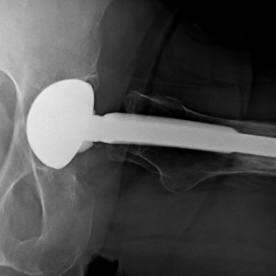

Röntgenbilder